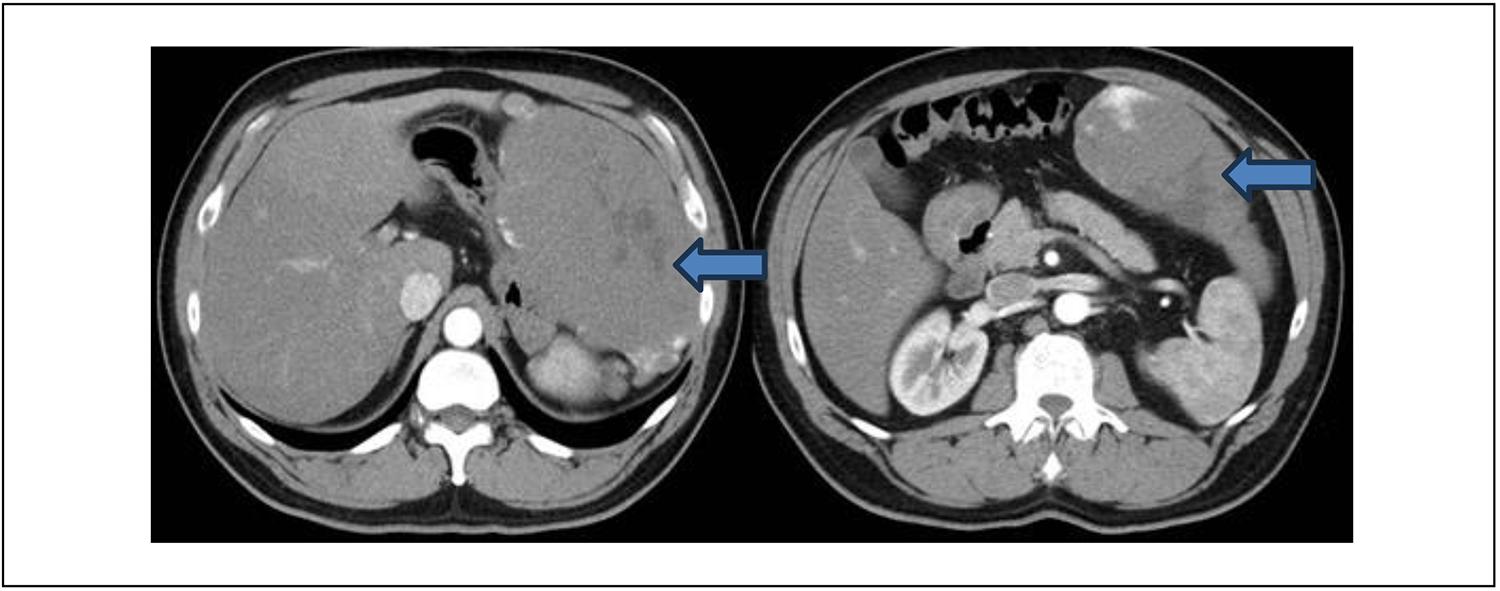

Los resultados de los análisis de sangre, incluyendo hemograma, enzimograma hepático, función renal y coagulación, fueron normales. La ecografía abdominal mostró un hígado heterogéneo con una lesión hiperecogénica en el lóbulo izquierdo. La tomografía computarizada de abdomen y pelvis con contraste endovenoso (TC) (Figura 1) reveló una imagen con características típicas de un hemangioma hepático: lesión voluminosa en el segmento II con captación de contraste discontinua y nodular periférica, con relleno centrípeto progresivo y longitudes de 179 mm x 97 mm x 174 mm. Por ello, se solicita Resonancia Magnética complementaria, (Figura 2) donde se visualiza dicha lesión hiperintensa en secuencia T2. Se identificaron dos imágenes hepáticas similares en los segmentos 6 (35 mm) y 7 (12 mm). No hubo dilatación de la vía biliar intra ni extrahepática.

Figura 1. Tomografía de abdomen y pelvis con contraste, donde se evidencia masa hepática en lóbulo izquierdo que desplaza y comprime estómago (flecha azul).La resonancia magnética abdominal confirmó la presencia de hemangiomas pequeños y un hemangioma gigante pediculado en el segmento II-III, presentando contacto con la pared abdominal, bazo y estómago, pero sin infiltración. (Figura 2).